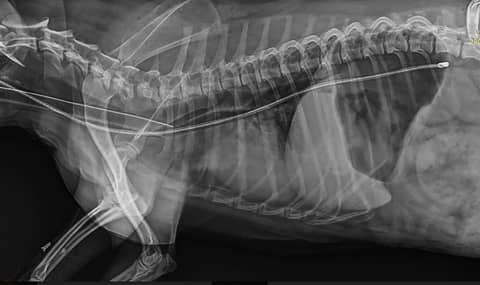

The Very Sneaky, Very Scary NG Tube Complication

From episode 163 on the ECC feed. With Dr Abbie Tippler and Dr Ellie Leister.What do you think about the placement of this NG feeding tube? Looks pretty good, right? Sitting nicely in the stomach. What if I t…